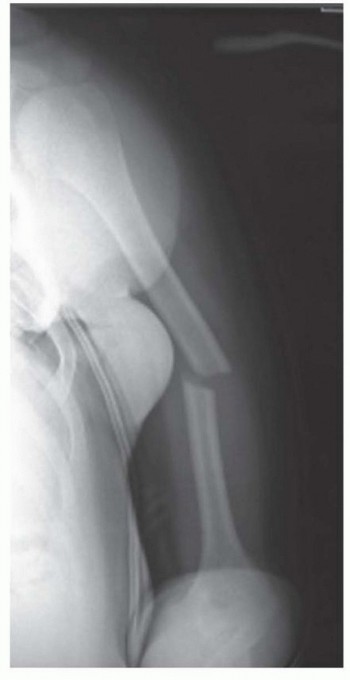

Chapter 22 Pediatric Hip Fractures Ernest L. Sink Benjamin F. Ricciardi DEFINITION Pediatric hip fractures co…